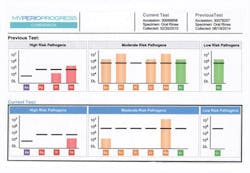

Before mechanical nonsurgical treatment was initiated, salivary diagnostic tests were performed to measure bacterial load and type. The test results (figure 2) confirmed the presence of eight bacteria associated with periodontal disease, including the high-risk Treponema denticola(T. denticola) and Tannerella forsythia (T. forsythia). The patient was prescribed trays containing 1.7% hydrogen peroxide (Perio Gel, QNT Anderson, Bismarck, ND) before treatment to use four times per day. Nonsurgical periodontal debridement and laser therapy were then initiated simultaneously over the course of four office visits. The patient used the prescription trays at least twice daily between the debridement with laser therapy appointments.

Tray delivery, four times daily for 15 minutes, began on August 21, 2014, for the first two weeks, and then two times a day for 15 minutes for the duration of treatment. Debridement, laser therapy, and subgingival irrigation were completed between September 9 and November 13, 2014. The patient continued to use the trays in maintenance therapy two times a day. At the February 20, 2015, maintenance visit, all pockets were within normal range except for four 4 mm pockets (figure 3). There was no bleeding, and a secondary diagnostic test confirmed a reduction in pathogenic oral bacteria.